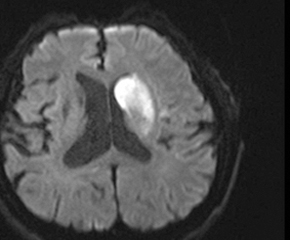

뇌경색 초기증상이 의심된다면 지금 바로 병원을 내방해 진단을 받고 적절한 치료를 손대는 것이 후유증을 감하는데 중요 해요. 시간이 관건이며, 뇌세포의 괴사, 증상 악화, 너무 늦으면 사망에 이를 수 있는 뇌혈관의 괴사를 피하기 위하여 증상이 나타난 뒤에 4시간 이내에 잘 맞은 약물, 시술 또는 수술을 신속히 실시해야 합니다. 치료로 즉시 하셔야 해요.